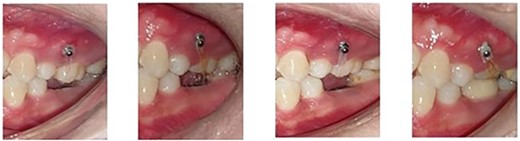

Orthodontic miniscrews measuring 1.6 mm in width and 8 mm in length, respectively, were placed. The screw on the buccal aspect was placed between the maxillary first molar and second premolar, and the one on the palatal aspect was placed between the first and the second molar (Fig. 1). The placement of the screws was planned in order to have a diagonal coverage of the occlusally directed forces for intrusion.

Placement of the miniscrews: (a) on the buccal side between the second premolar and the first molar and (b) on the palatal side between the first and the second molars; composite button on the occlusal surface to direct the forces along the long axis.

Following the placement of miniscrews, immediate loading was done with 100 g of intrusive force using a short power chain. The power chain was passed and engaged onto the composite button to ensure the forces are directed occlusally and there is no slippage. The patient was followed up at 4-week intervals and the power chain was replaced with one link, which was reduced at each appointment. After the first month, the dental implant was placed to replace the mandibular first molar. After 5 months of intrusion, the desired occlusal clearance was achieved and the upper and lower impressions were recorded (Fig. 2). For retention in the upper arch, the patient was given a clear vacuum retainer, while the crown was placed on the implant to prevent any relapse and to achieve good occlusion.